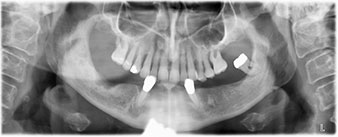

Para la planificación y la minimización del riesgo, se realizó una tomografía volumétrica tridimensional (TVD, Planmeca) que mostró que la calidad y la cantidad del tejido óseo era suficiente para la intervención quirúrgica y el tratamiento inmediato con el método Fast & Fixed. Siguiendo el protocolo de este método, se insertaron los implantes en la región de las piezas 35, 32, 42 y 45. Debido a la inclinación de hasta 45 grados de los implantes distales, el perfil de emergencia se desplazó hacia posterior y se generó un mayor polígono de soporte (fig. 3).

El protocolo quirúrgico de los implantes utilizados (SKY, bredent medical) prescribe una velocidad de 1 200/rpm para las perforaciones piloto (figs. 7-9).

Este valor se corresponde con la posición siguiente del ajuste predefinido en Implantmed. Aquí se aprecia la inclinación de aproximadamente 45 grados del contra-ángulo de W&H hacia medio caudal en la región de la pieza 45 para preservar el nervus mentalis. El foramen mentale sirve como orientación anatómica para todas las perforaciones en esta zona. Las perforaciones siguientes se realizaron con una velocidad reducida de 300/rpm (figs. 10 y 11).